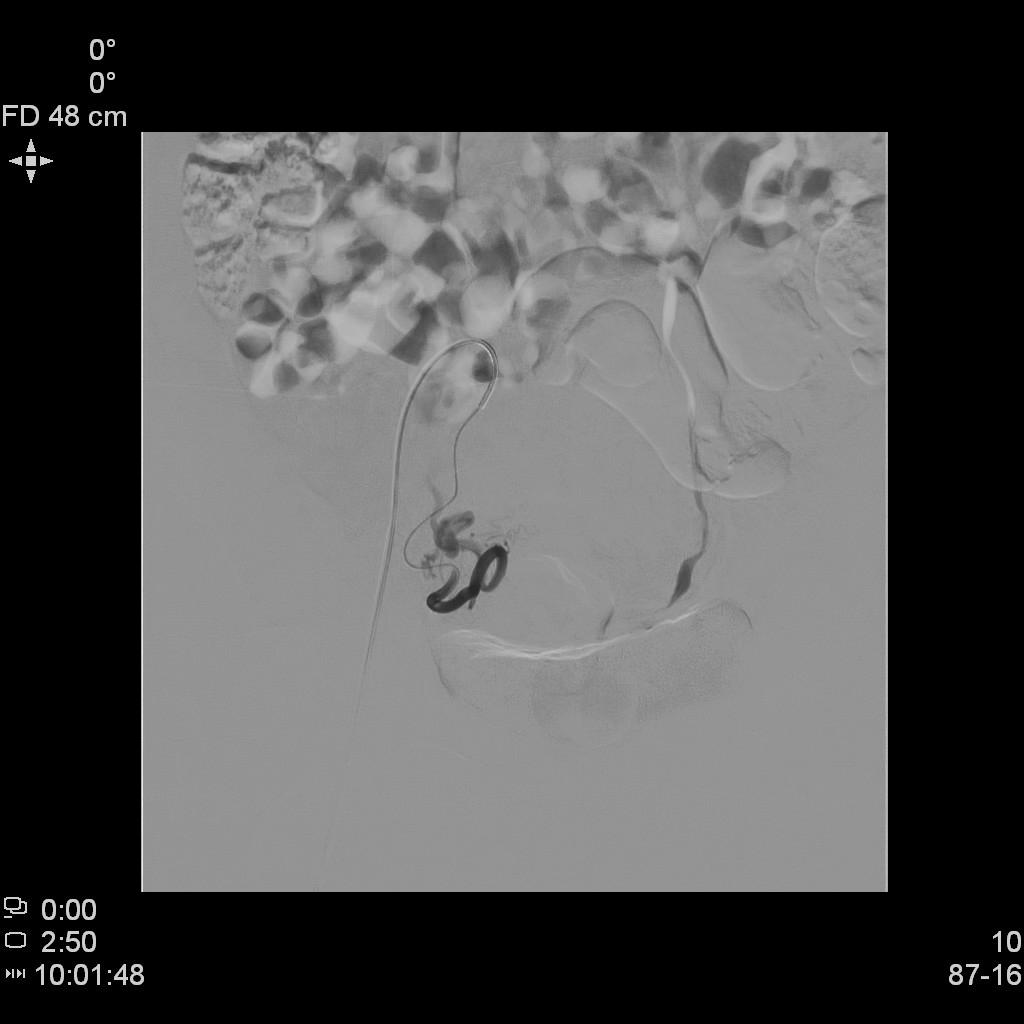

- DSA下行双侧子宫动脉栓塞治疗。

左侧子宫动脉造影

右侧子宫动脉造影

- 经桡动脉入路,分别超选择插管至双侧子宫动脉造影+子宫肌瘤栓塞治疗。